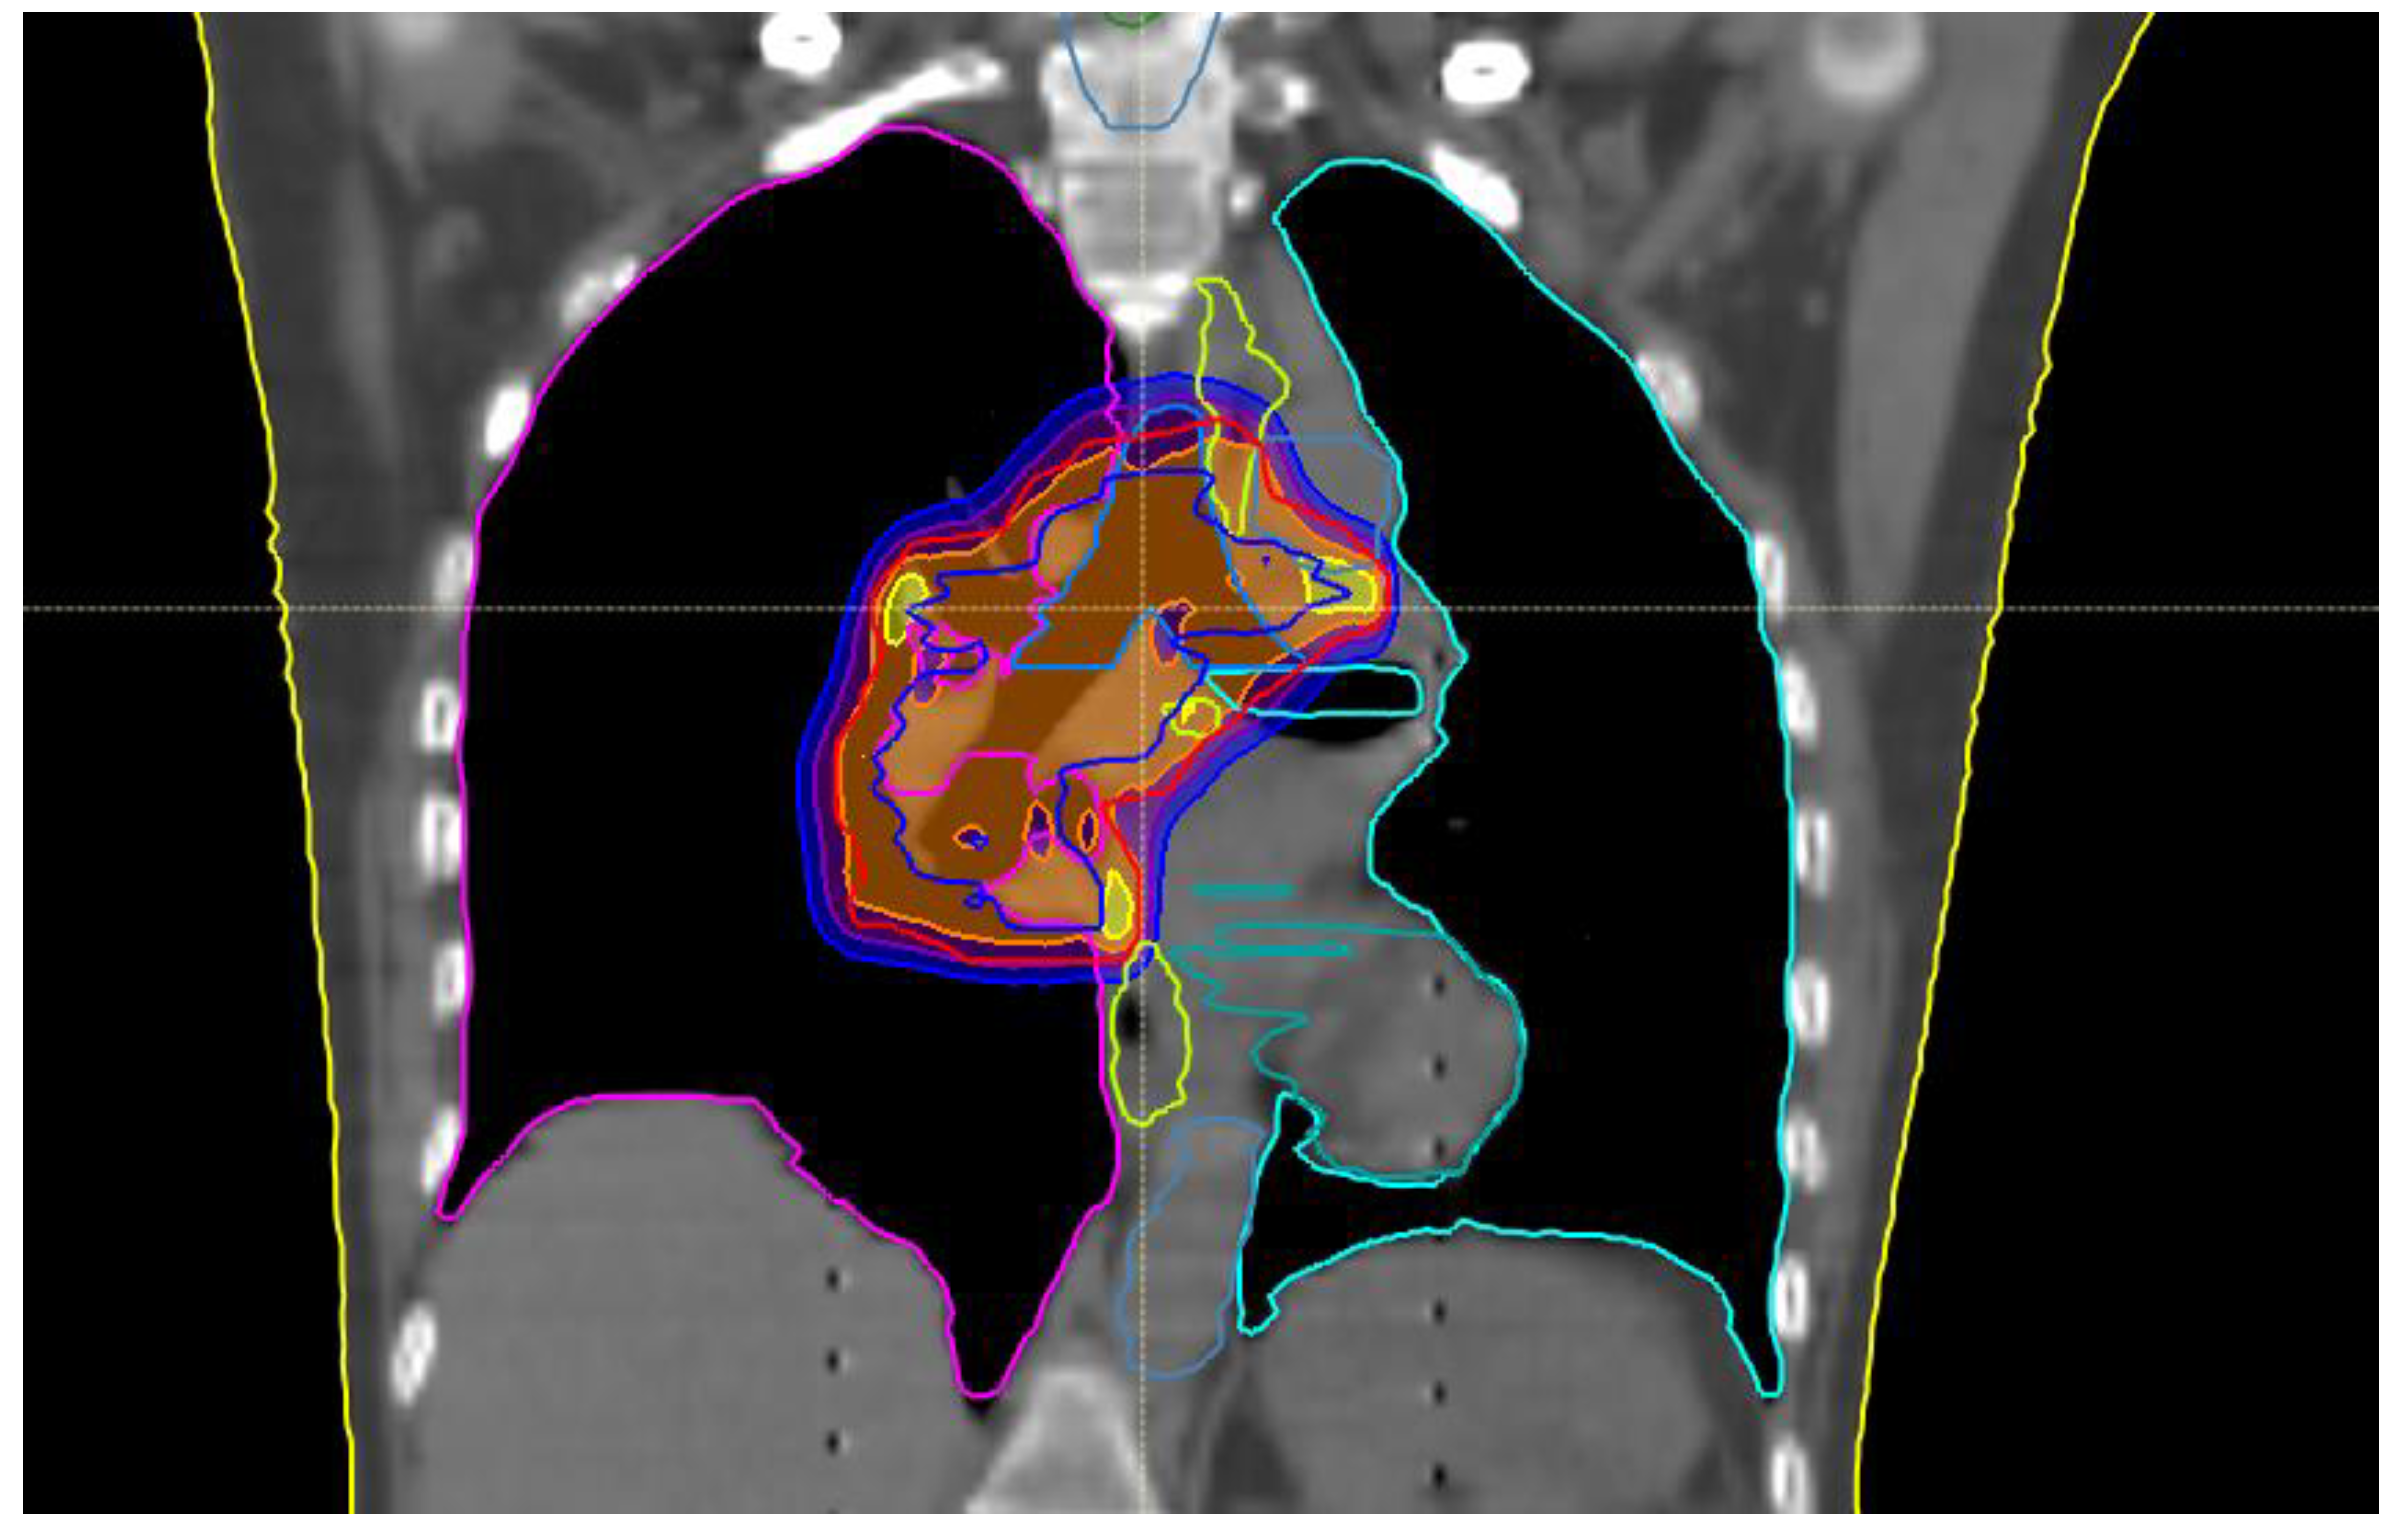

Total body computed tomography (CT) scan was performed almost 30 days after the last session of RT showing partial response of the right hilar nodes and no further disease metastasis. Thus, the patient underwent consolidative IO with durvalumab (first dose in January 2020). In October 2020, a restaging CT scan showed stable disease of the thoracic lesion, while a single rounded frontal cortical contrast enhanced small lesion at the vertex (diameter of about 8 mm) appeared. The same cerebral metastasis was confirmed by contrast enhanced brain magnetic resonance (MR) with no other intracranial lesions. In the meanwhile, she received the last planned dose of durvalumab (22 cycles). The case was then referred to our lung multidisciplinary meeting team and it was recommended to proceed with single session SABR (December 2020) to the left frontal brain lesion for a total dose of 20 Gray (Gy). Image guided with intensity modulated RT was performed. (Figure 2). Both treatments (systemic and SABR) were well tolerated and no side effects were reported. Her quality of life was always well maintained.

Figure 2.

Treatment plan for single session brain SABR (a) sagittal and (b) coronal reconstruction.